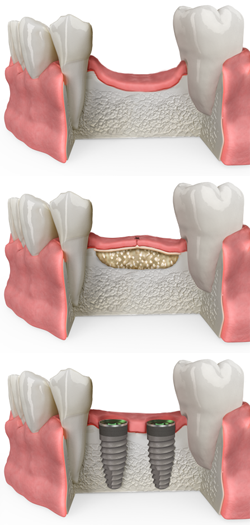

Missing teeth can lead to a number of problems, including bone loss in your jaw. This bone loss can make it difficult to replace missing teeth with dental implants, a permanent and natural-looking solution. At Dental Elements, your trusted dentist in Downtown Denver, we offer dental bone grafting to restore bone volume and create a strong foundation for successful dental implants.

Dental bone grafting is a surgical procedure used to rebuild lost bone in the jaw. This bone can be taken from another location in your own body (autograft), donated by a tissue bank (allograft), or derived from synthetic materials. The grafted bone is then placed in the area where bone has been lost and allowed to heal. Once healed, the bone provides a stable base for the placement of dental implants.